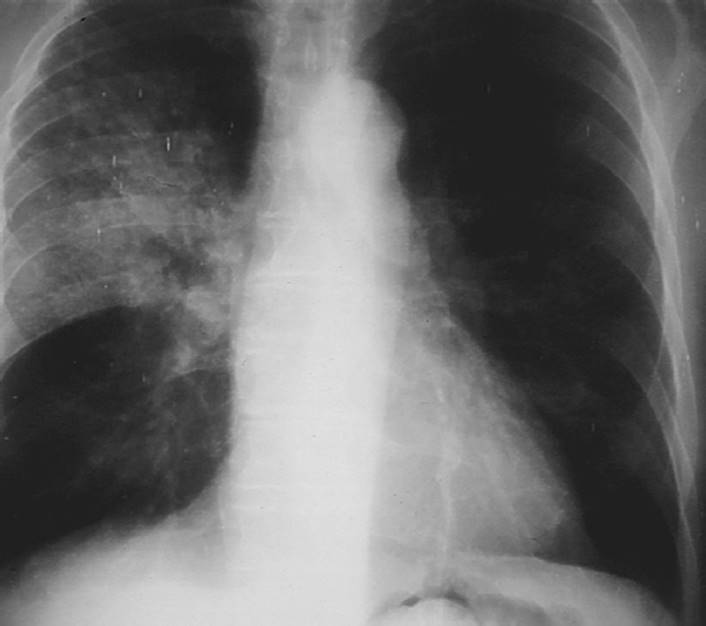

CF is the most common autosomal recessively inherited disorder in Caucasians.69 Within the lungs, this genetic defect leads to excessive production of thick, dehydrated, hyperviscous mucus and impairment of the mucociliary blanket.70,71 The incidence is 1 in 3,000 births in the United States and Europe. Chronic bouts of inflammation and infection lead to the breakdown of protein in the lungs. Obstructions of small airways develop from mucus plugs and destruction of the cartilaginous support of the airways. The end result is bronchiectasis, which is a permanent dilatation of the bronchi that is characterized by inflamed airways, which are full of purulent sputum23 (see Figs. 7-11and 7-12).

FIGURE 7-12 Cystic fibrosis. This gross pathology slide clearly illustrates destruction of the parenchymal tissue and the large cyst formation. (Courtesy of Dana Gryzbicki, MD, University of Pittsburgh, PA.).